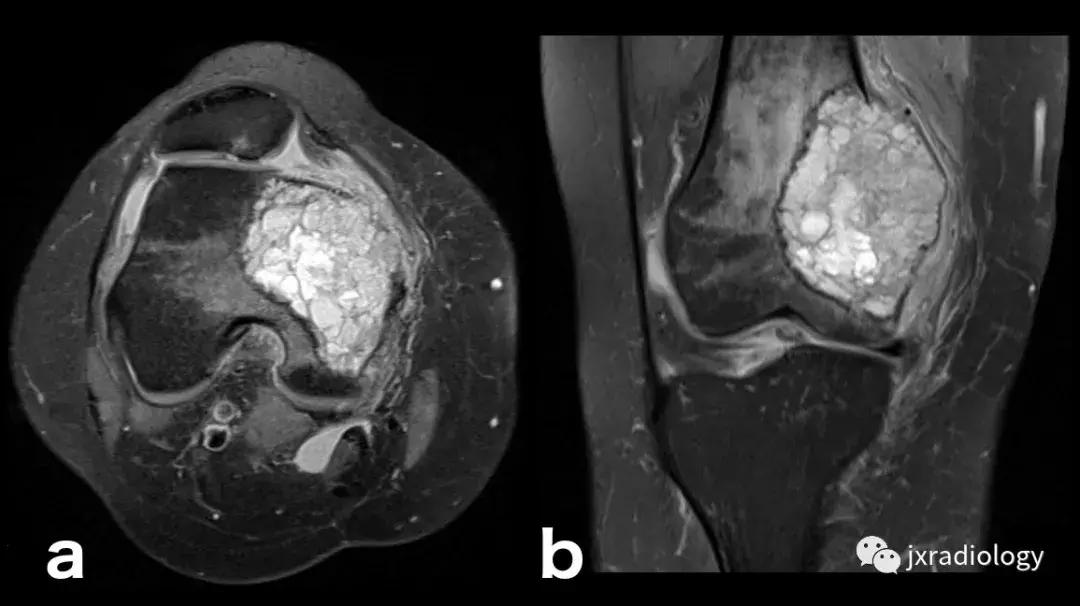

图22:骨肉瘤(a,b:冠状和轴向PD-FS-WI):肿瘤性水肿继发于骨小梁破坏引起的直接毛细血管损伤,并伴有血管内液体释放和出血。 区分周围水肿和肿瘤侵袭可能是困难的。

图23:骨巨细胞瘤(PD-FS-WI):也存在肿瘤性骨髓水肿。